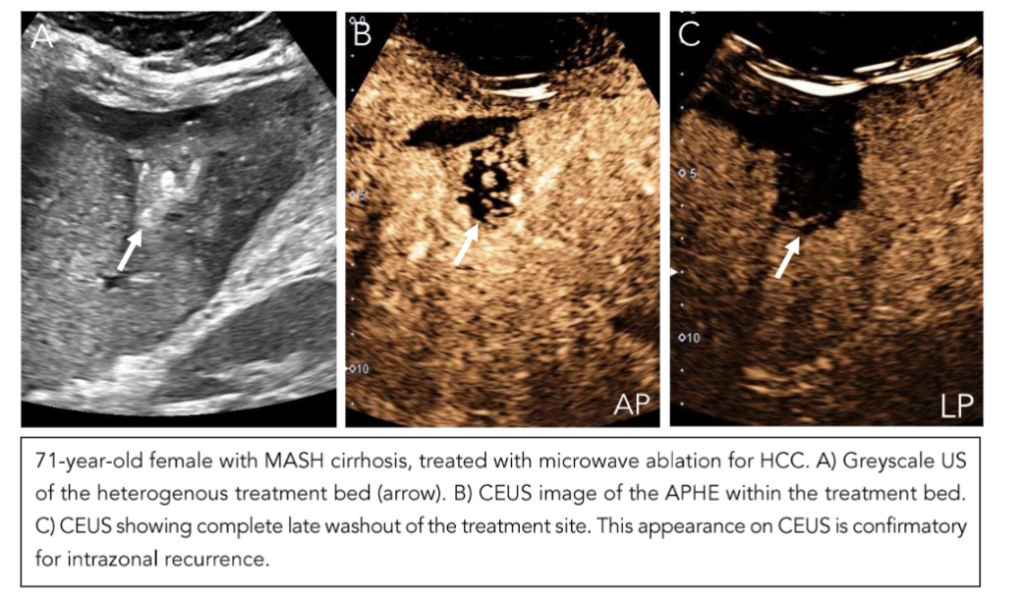

The observations in the secondary surveillance period follow the CEUS LI-RADS treatment response algorithm (TRA)(52). In a technically adequate exam, the ablation site is assessed for both intralesional and perilesional tumor viability. For intralesional viability, if there is no enhancement within the ablation bed, it indicates the absence of a viable tumor. Uncertain viability is characterized by arterial phase hyperenhancement (with or without washout), while hyperenhancement or isoenhancement (with or without washout) suggests the presence of a viable tumor (Figure 10). For perilesional viability, absent viability is characterized by homogeneous enhancement of the ablation margins compared to the rest of the liver. Uncertain viability is characterized by arterial phase hyperenhancement without washout, isoenhancement with washout, or hypoenhancement. The presence of a viable tumor is confirmed by hyperenhancement with washout (Figure 11). Once both these categories are assessed, an overall treatment response score is determined based on their respective contributions. If there is any intralesional or perilesional viability, the overall treatment response score is LI-TR viable. If there is any uncertainty in one without viability present in the other, the overall treatment response score is LR-TR equivocal. Here, an alternative imaging modality like MRI would be useful in clarifying the viability. Only when there is absent viability in both intralesional and perilesional viability is the final category designated as LR-TR nonviable (Figure 12).

Figure 10: Intralesional Recurrence